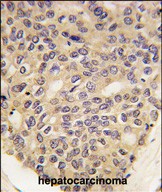

- Formalin-fixed and paraffin-embedded human hepatocarcinoma tissue reacted with PINK1 Monoclonal Antibody (Cat.#P30246), which was peroxidase-conjugated to the secondary antibody, followed by DAB staining. This data demonstrates the use of this antibody for immunohistochemistry; clinical relevance has not been evaluated.